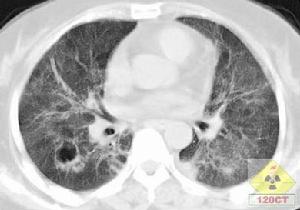

沙雷菌肺炎體徵

沙雷菌肺炎2.體徵雙肺可聞及乾濕性囉音,當肺葉或肺段出現實變時,可有相應肺段、肺葉的語顫增強,叩濁、可聞及支氣管呼吸音。危重病人可能有呼吸急促、發紺及休克等。